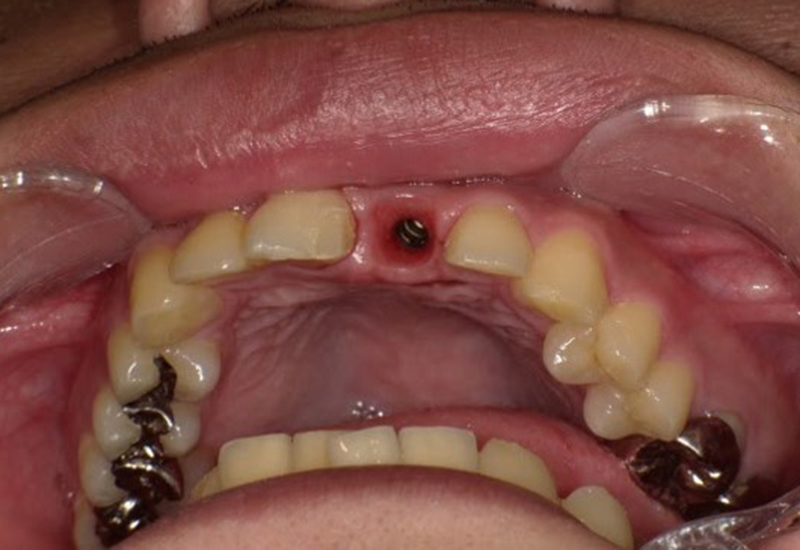

手術の様子

![]() |